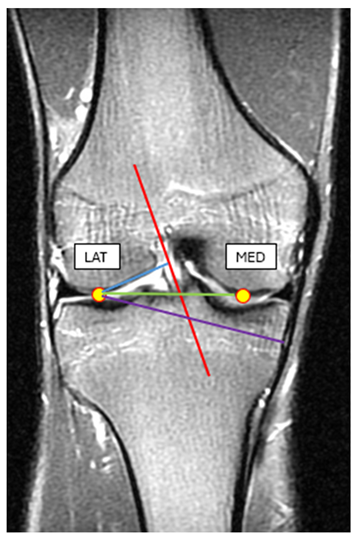

To reach our goal we have also collected MRI images and anthropometric data of 15 healthy male individuals (age 19-23, BW=80.2±6.8kg). In the MRI images of the knee we have identified the lateral and the medial condyles and using the MRI image software (RadiAnt DICOM Viewer) measured the lateral condyle-ACL distance, lateral condyle-MCL distance, lateral condyle-medial condyle distance (Picture 1.). For the required anthropometric data, we have measured the ground-lateral condyle and the lateral condyle-greater trochanter distance respectively (Picture 1,

Table 2).

Table 2.

Average and SD of measured variables for the athletes. MRI images were used to determine the values for the internal section of the knee.

Measured variables (distances) |

Lateral condyle-ACL (mm) |

Lateral condyle-MCL (mm) |

Lateral condyle-medial condyle (mm) |

Ground-Lateral condyle (mm) |

Lateral condyle-greater trochanter (mm) |

| Average |

26,06 |

68,8 |

58,46 |

594,86 |

461,8 |

| SD |

1,7 |

3,27 |

2,82 |

13,89 |

9,33 |